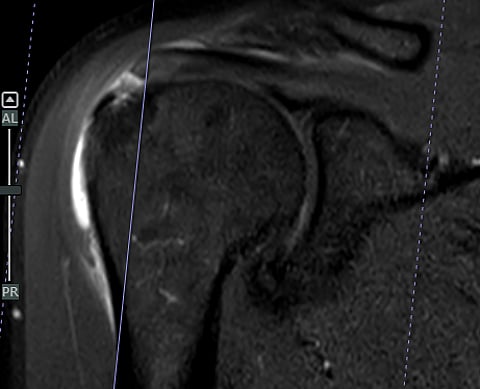

حقق قسم جراحة العظام في مستشفى المانع – فرع الخبر إنجازًا طبيًا لافتًا، بقيادة الدكتور محمد المجتبى ، بعد أن تمكن مريض يبلغ من العمر 61 عامًا من استعادة كامل مدى الحركة في كتفه خلال أربعة أسابيع فقط من خضوعه لعملية إصلاح الأوتار بالمنظار باستخدام رقعة الكولاجين التعويضية، وهي تقنية طبية حديثة تُستخدم لتعزيز التئام الأوتار وتسريع عملية التعافي.

وتُعد هذه النتيجة استثنائية مقارنة بالعمليات التقليدية لإصلاح الأوتار، والتي قد يستغرق التعافي الكامل بعدها ما يصل إلى ستة أشهر، في حين تمكن المريض في هذه الحالة من العودة إلى حياته الطبيعية دون آلام أو ضعف خلال شهر واحد فقط.